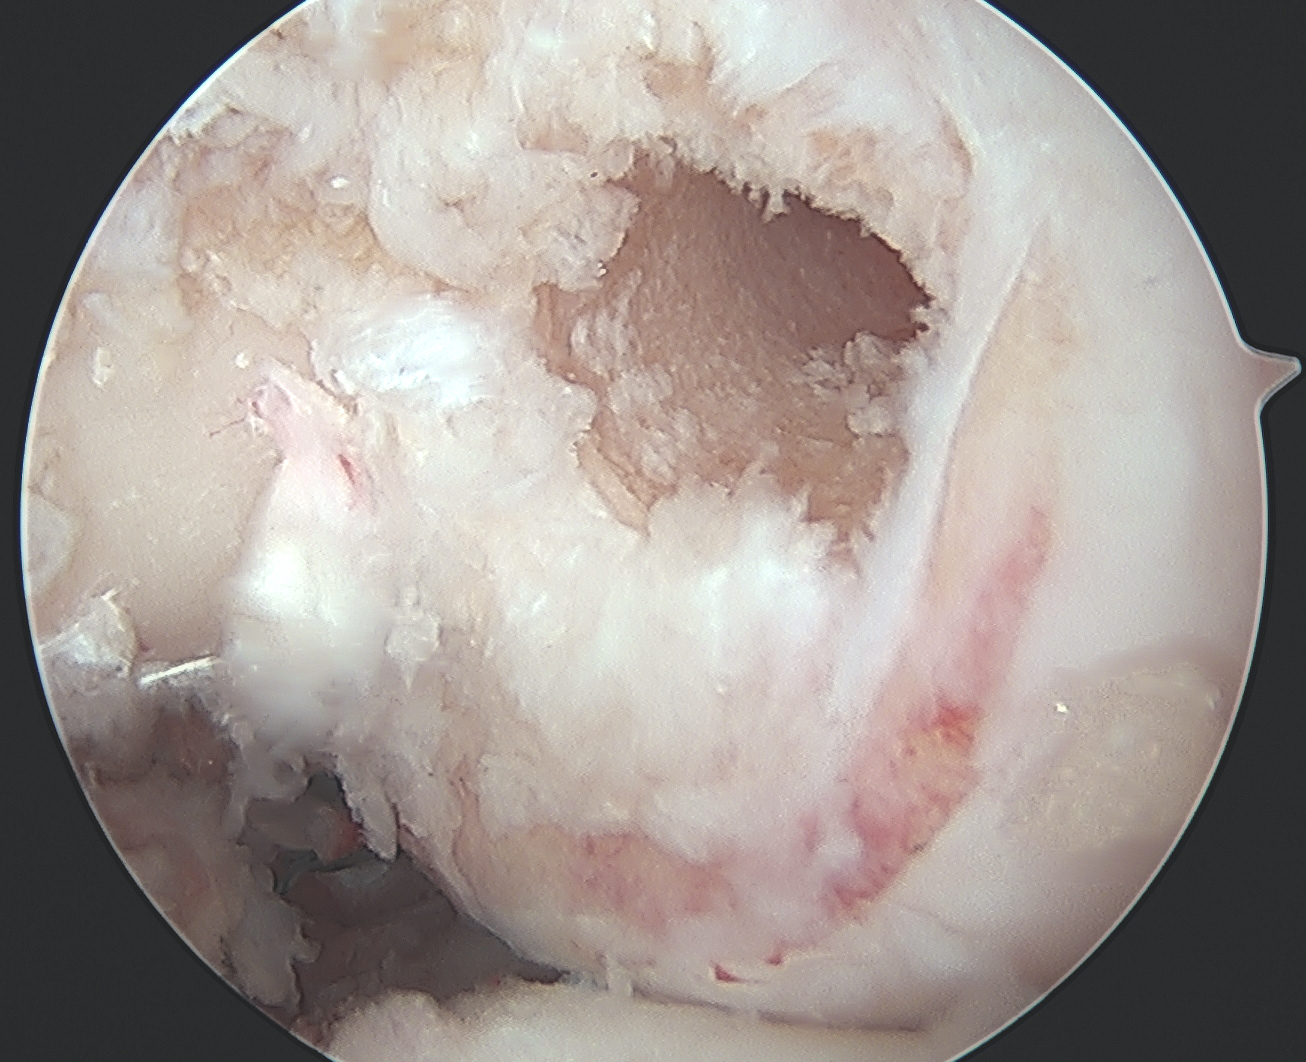

Need adequate visualisation of the PCL facet

- down at least 1 - 2 cm below articular surface

- combination of shaver and electrocautery

- usually need to release some of the capsular insertion onto posterior tibia

PCL facet 1PCL tibial tunnel

PCL tibial facet                                                           Tibial tunnel beath pin

Tibial Tunnel

Incision medial to tibial tuberosity

- PCL jig inserted, usually set at 60 or 65o

- under fluoroscopy, identify the PCL facet

- at least 1 cm below the articular surface

- needs to be more lateral than medial to recreate the anterolateral bundle of PCL

- curette inserted to protect NV bundle

- knee in flexion to protect NV bundle

- beath pin passed

- ream appropriate tunnel (9 or 10 mm for achilles tendon allograft)